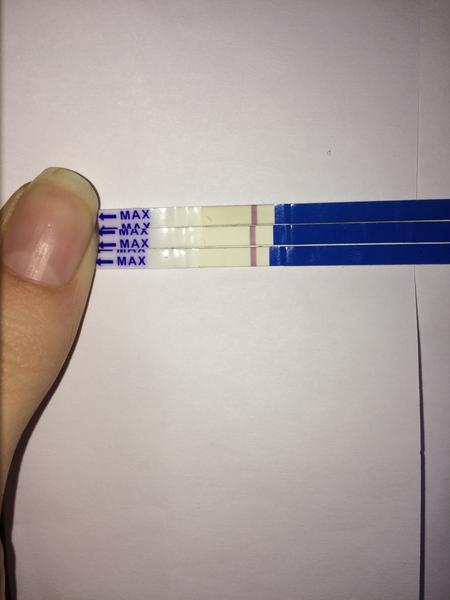

Těhotenský test. Dávám fotku. Co myslíte?

dnes jsem si dělala testík...

První byl ClearBlue a téměř hned tam naskočilo plus.

Udělal jsem radši ještě jeden - jmenuje se ForYou... Tam se objevil slabý duch, ale až tak za 3minuty! Šla jsem ven se psi a když jsem se vrátila, tak duch byl silnější...no ale to bylo skoro po půl hodině!

Tak nevim ... ☹ Dávám fotku, skuste posoudit...